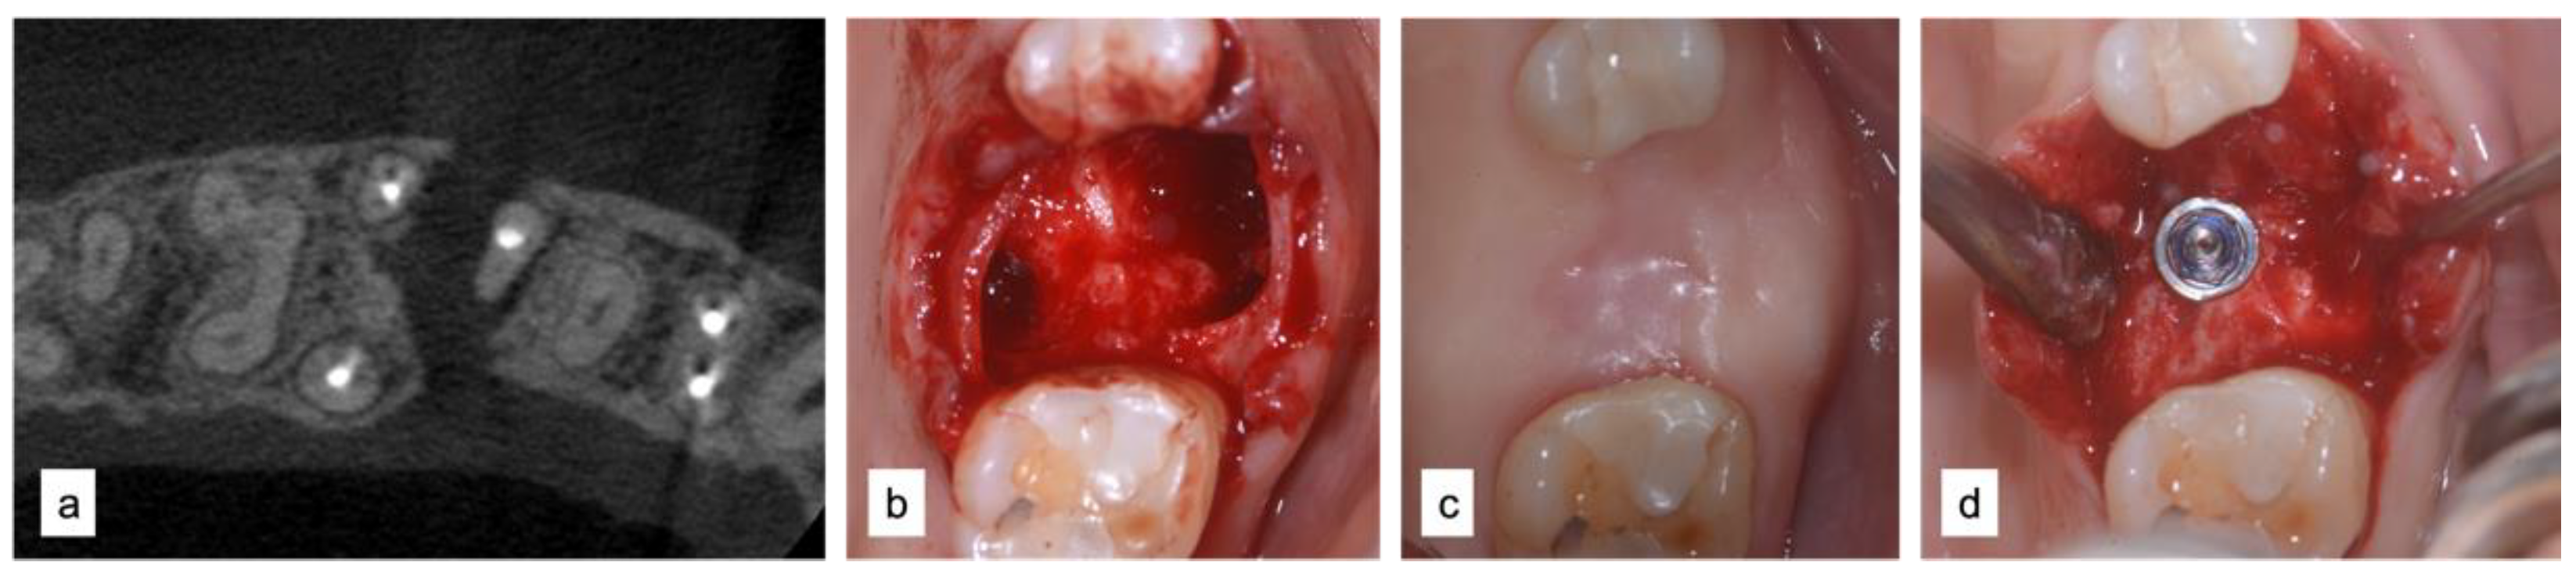

2.2.1. Case 1—MPI Technique Zone 47